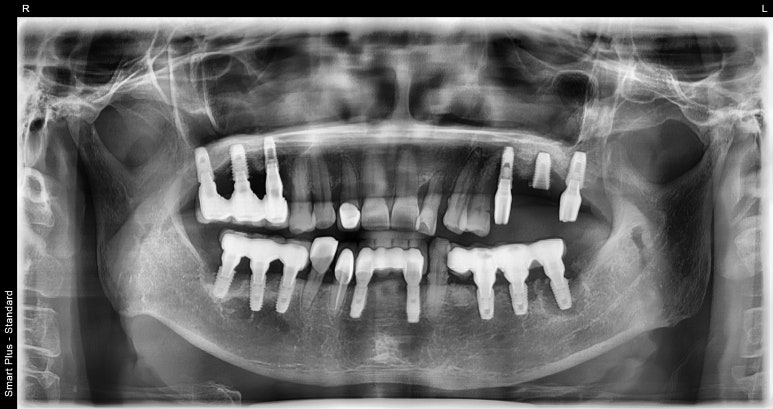

보시다시피 사진 상 오른쪽 아래 어금니(실제로는 왼쪽 아래)쪽 임플란트 주변에 염증이 관찰되는 것을 확인하실 수 있습니다.

이렇게 임플란트주위염이 생겨 심해질 경우 잇몸뼈가 녹아내려 임플란트를 지탱하는 기반이 약해집니다.

그렇게 되면 임플란트한 치아가 흔들리고 제 기능을 할 수 없게 되겠죠.

이번에 내원해주신 환자분도 엑스레이 사진상으로 확인이 가능할 정도로 염증이 심해지신 상태였고

이 상태에서는 임플란트가 제 기능을 하기 어려워 제거 후에 다시 식립하기로 했습니다.